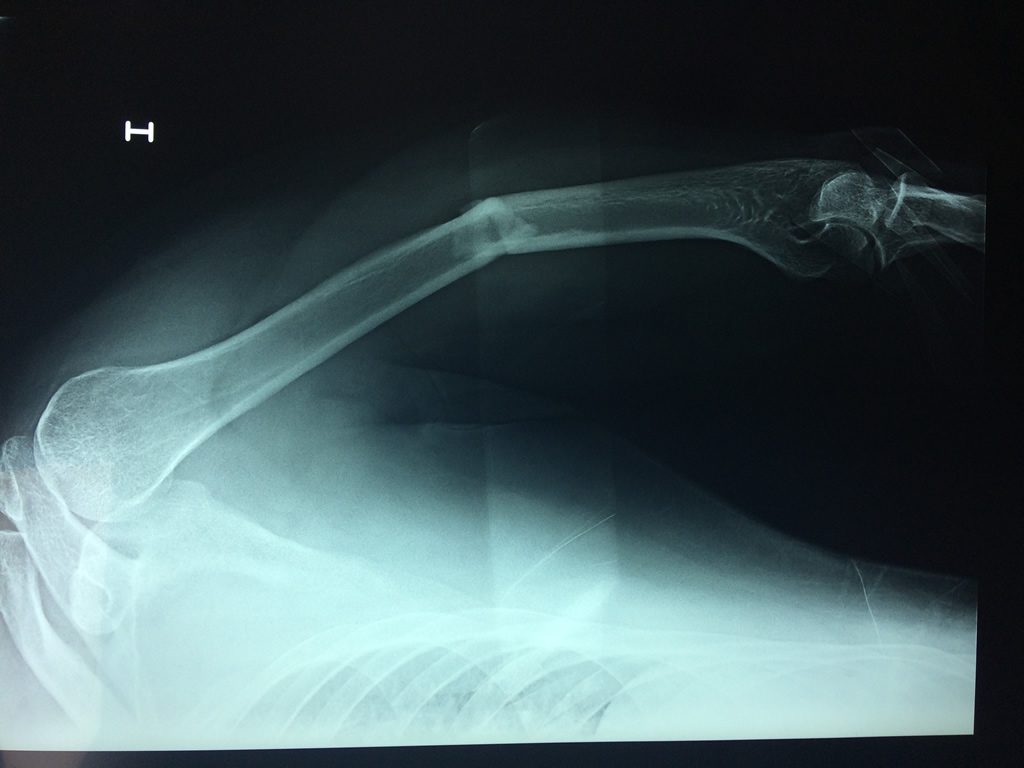

Cirugías de Peroné y Tibia

El Húmero (en latín, humerus) es el hueso más largo de las extremidades superiores en el ser humano. Forma parte del esqueleto apendicular superior y está ubicado en la región del brazo. ... El extremo proximal del húmero tiene la cabeza, cuellos quirúrgico y anatómico y tubérculos mayor y menor.